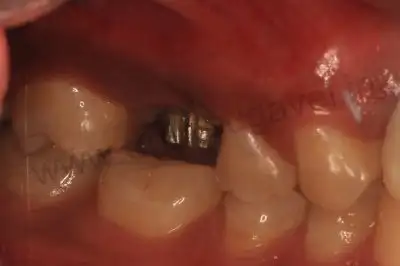

Implant in right upper molar

Side view of implants

On day 1 :

- Prophylactic medications given.

- Computerized anesthesia local infiltration given in 16 region

- Key hole implant surgery done and one implant placed.

- For better osseointegration , the implant is synchronised with titanium bar and intra oral digital scanning done for CAD CAM crown.